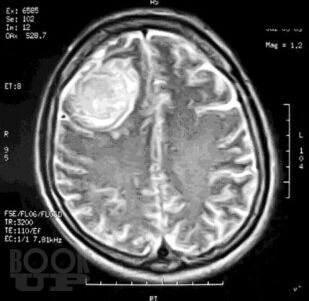

Нейроонкология. Опухоли центральной и периферической нервной системы

В учебном пособии представлена клиническая картина, диагностика опухолей головного и спинного мозга. Особое внимание уделено топической диагностике. Предназначено для неврологов, врачей общей практики (семейных врачей), терапевтов, нейрохирургов.